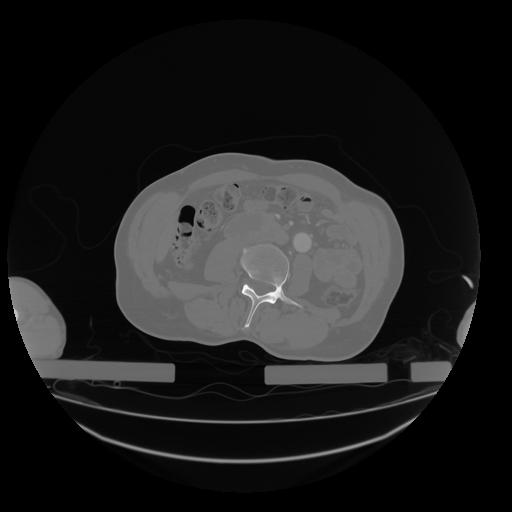

28 CUERPO,CE,Vol,2.0,CUERPO,,